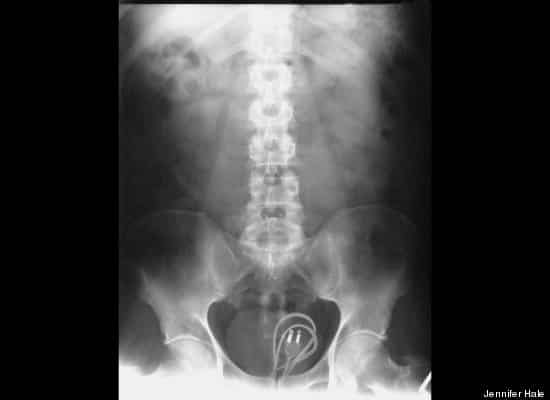

8. Un câble de chargeur

Si vous n’avez plus de place pour ranger votre câble de smartphone, regardez cette image.

câble

(source photo : le Huffington Post)